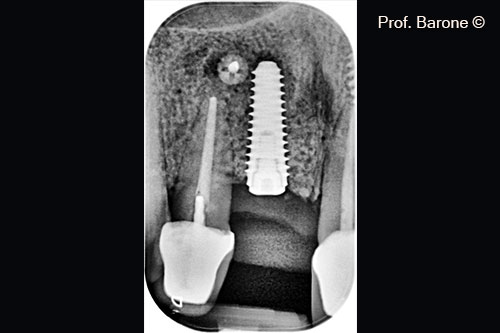

Hình ảnh X-Quang quanh chóp răng 3 tháng sau khi cấy ghép implant